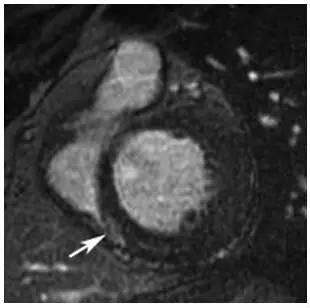

入院辅助检查:血常规:白细胞7.72×10^9/L,血红蛋白169g/L,血小板270×10^9/L;尿常规+沉渣未见异常;24 h尿蛋白0.09g;肝肾功能均正常;血脂:胆固醇4.35 mmol/L,三酰甘油2.43 mmol/L,高密度脂蛋白胆固醇1.03mmol/L,低密度脂蛋白胆固醇2.59 mmol/L;甲状腺功能正常;脑钠肽52ng/L;抗核抗体19项、抗中性粒细胞胞浆抗体均阴性;血清蛋白电泳:M蛋白19.2%,M蛋白15.10g/L;血免疫固定电泳:IgGκ(+);血游离轻链:κ/λ3.1(0.26~1.65);尿免疫固定电泳:游离κ阳性;血涂片:红细胞大小不等,呈缗钱状;骨髓涂片示浆细胞比例稍高(成熟浆细胞3.5%),形态正常。骨髓活检:骨髓中造血组织略增多,刚果红染色(-)。腹壁脂肪活检:刚果红染色弱阳性,κ和λ(-);齿龈、舌体活检:刚果红染色阴性。X线片:心影增大;头颅、骨盆、肱骨、股骨正侧位均未见异常。腹部超声:轻度脂肪肝;胸腹盆CT:双上肺偶见肺大泡。冠状动脉造影:前降支第一对角支近段管状狭窄最重50%,TIMI血流Ⅲ级;右冠状动脉后降支近段局限狭窄80%,TIMI血流Ⅲ级。心脏磁共振:左心室增大,左心室心肌略厚,LVEF35.4%,室间隔基底部及中部可疑灌注减低,室间隔与右心室下壁连接部位似见片状延迟强化(图1),心肌病变不除外。肌电图:双上肢神经源性损害(慢性)。睡眠呼吸监测:中度阻塞性睡眠呼吸暂停低通气综合征,侧卧位减轻。

图1 心脏磁共振显像(延迟钆增强)示室间隔与右心室下壁连接部位似见片状延迟强化(箭头所示)